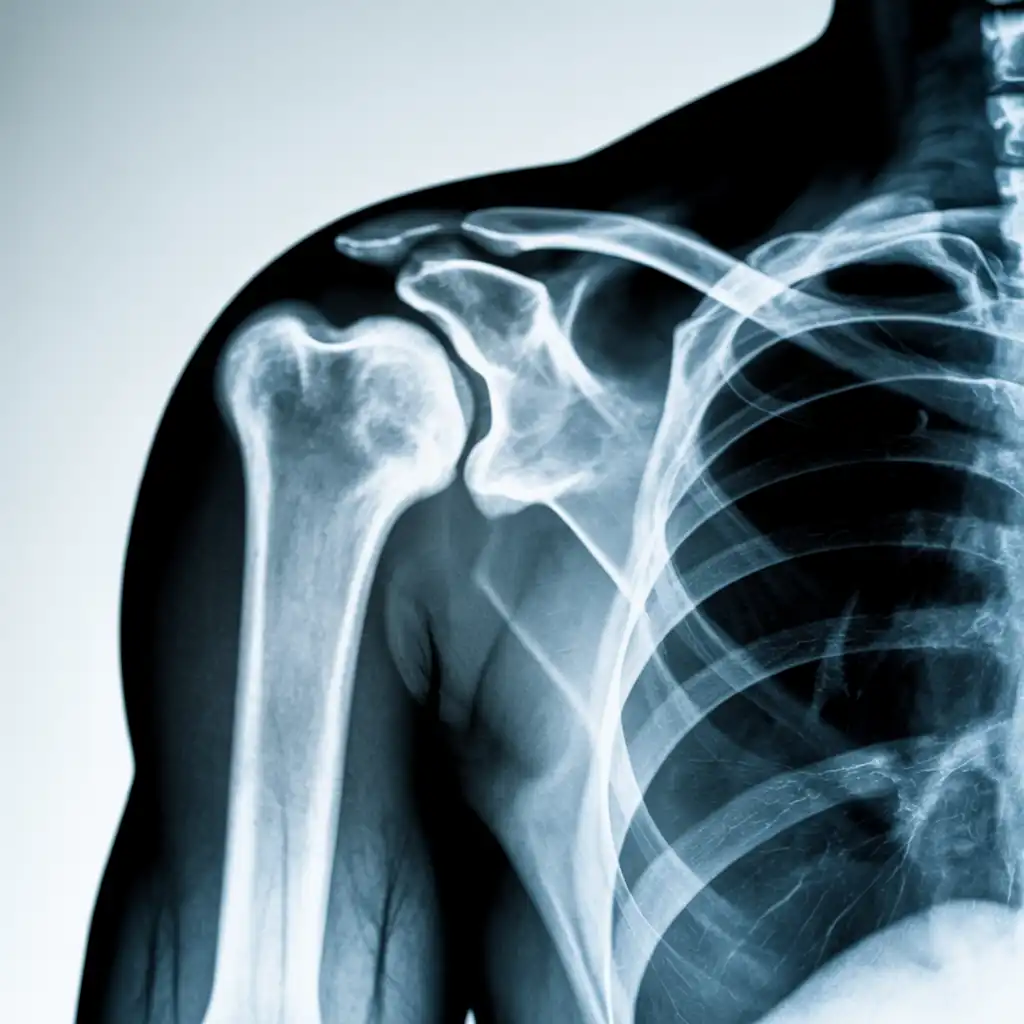

Una lastra a domicilio è una radiografia eseguita direttamente a casa del paziente, grazie all’intervento di un tecnico sanitario qualificato dotato di apparecchiatura digitale portatile.

L’esame viene effettuato sul posto, senza necessità di spostare la persona dal letto o dalla poltrona, e garantisce una qualità diagnostica paragonabile a quella di un reparto ospedaliero.

Una volta acquisite, le immagini vengono trasmesse al medico radiologo, che le analizza e redige il referto in tempi brevi.